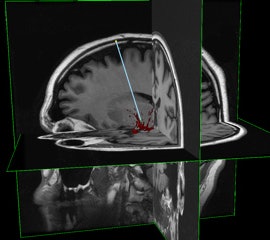

A gadolinium-based contrast agent is added so that drug delivery can be tracked on MRI.

"We use [gadolinium] as a marker, and by doing a series of MR images, we can quantitatively determine the tracer concentration and thus determine whether gene therapy has been delivered," Block said.

So far, the company has successfully guided convection-enhanced delivery procedures in vivo in swine brains, as well as five gene delivery procedures in a nonhuman primate model.

The software platform has achieved millimeter accuracy in catheter placement and monitoring infusions as small as 12 mL, Block estimated.